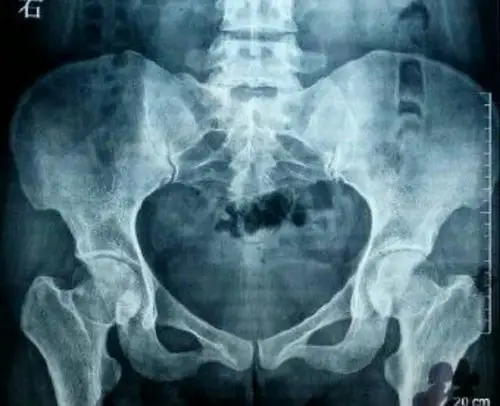

骨盆x光片分析(站立位),看片不求人

正常骨盆正位片x线解剖

术前骨盆正位x线检查

正常骨盆x光片

脊柱,髋关节,骨盆x光正面图.